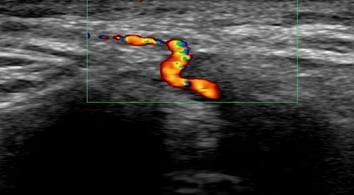

Ultrasound of the temporal arteries is used to help diagnose GCA, because it can non-invasively visualize characteristic features of the disease. Specifically, ultrasound can detect a "halo sign," which is a thickening of the artery wall, as well as stenosis (narrowing) or occlusion (blockage) of the artery. These findings can help confirm or exclude the diagnosis of GCA, potentially avoiding the need for a temporal artery biopsy in some cases.